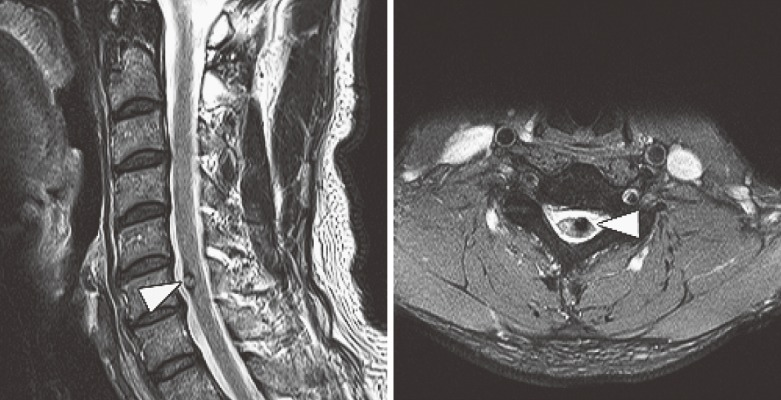

脑干海绵状血管瘤案例:脑干CCM手术从简单的概念开始,如“两点法”来选择较佳的手术方法复杂颅骨基地曝光肿瘤和动脉瘤的发展是适应的病理CCMs(图2...

脊髓髓内海绵状血管瘤占全部脊髓血管病变的5%-12%。症状性CH的临床过程具有侵袭性,出血率高,因此建议手术切除。通常通过后部或后外侧入路进行脊髓...

脑干海绵状血管瘤核磁共振 MRI是诊断海绵状血管瘤的重要辅助检查。通过MRI检查可以明确瘤体位置、大小及其与周围结构的关系。海绵状血管瘤在MRI的检查...